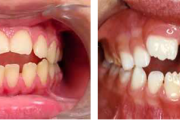

Turritavad ülemised lõikehambad.

prognaatne hambumus, ülemised eeshambad on ettepoole alumiste suhtes ja eest

ettepoole ulatuvad ülahambad